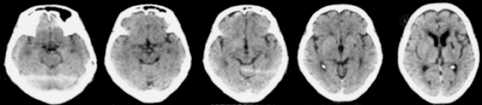

患者女性,72岁,主因渐进性右肢力弱9个月、记忆力减退3个月、错认1周于2015年6月17日入天津市环湖医院。患者于入院前9个月渐感做家务时右手无名指、小指力弱,遂就诊于天津市某综合医院,行头颅CT检查(图1),考虑脑梗死,给予输液治疗2周,此症状渐进性加重,累及中指及右手。于入院前3个月,患者因右手持物力弱、右下肢行走无力、记忆力减退、近期发生过的事情记不起来,再次就诊于天津市某中医医院,行头部MRI检查(图2),FLAIR序列可见双侧颞叶内侧面、海马区高信号影。按照脑梗死给予输液治疗,并口服阿司匹林、阿托伐他汀治疗。于入院前1周,患者右肢无力较前加重,右手持物不稳,右下肢站立及行走需搀扶,并数次跌倒。家属发现其偶有面孔错认,把自己的亲人认错。为进一步诊治收入院。自发病以来,患者无明显头痛及头晕,无视物旋转及视物成双,无恶心呕吐,无耳聋耳鸣,无肢体麻木及抽搐,无意识障碍,存在情绪低落、兴趣减少、食欲下降,体重3个月内减轻5 kg。既往史:有高血压病史20余年,血压最高达160/100 mmHg (1 mmHg=0.133 kPa),平时口服缬沙坦80 mg (1次/d)降压治疗,血压维持在120~130/90 mmHg。入院后神经科体检:意识清楚、构音障碍,双瞳孔等大等圆,光反射(+),眼动可,眼位居中,无眼震及复视,右侧鼻唇沟稍浅,伸舌尚居中,颈软,右肢肌力Ⅳ级,左肢肌力Ⅴ级,肌张力可,腱反射(++),双侧巴宾斯基征(-),右面部及右侧肢体浅感觉异常,双侧共济检查稳准。高级神经活动认知功能检查:简易精神状态检查评分12分,蒙特利尔认知评估量表评分7分,定向力、回忆能力、计算力、语言重复流畅性、执行功能、视空间结构等领域均受累。实验室检查阳性结果:血常规示中性粒细胞百分比83.0%(正常值40%~75%),血小板计数68×109/L[正常值(125~350)×109/L];红细胞沉降率37.00 mm/h(正常值0~15 mm/h),乳酸脱氢酶265 U/L(正常值135~225 U/L];甲状腺功能全项:三碘甲状腺原氨酸1.00 nmol/L(正常值1.3~3.1 nmol/L);血液三项:叶酸4.08 ng/ml(正常值4.6~34.8 ng/ml)。超敏C反应蛋白、乙型肝炎、梅毒血清学检查结果正常。肺癌和肝脏、胃肠、盆腔肿瘤标志物检查结果正常。入院后行腰椎穿刺检查,压力200 mmH2O(1 mmH2O=0.009 8 kPa);脑脊液常规:总细胞数382×106/L,白细胞数2×106/L[正常成人(0~8)×106/L] ;脑脊液生化:氯化物117 mmol/L(正常值120~132 mmol/L],蛋白1.18 g/L(正常值0.15~0.45 g/L),乳酸5.4 mmol/L(正常值0.6~2.2 mmol/L)。脑脊液免疫功能:白蛋白714.00 mg/L(正常值0~350 mg/L),免疫球蛋白A 6.89 mg/L(正常值0.1~5 mg/L),免疫球蛋白G 56.30 mg/L(正常值0.1~34 mg/L),免疫球蛋白M 2.68 mg/L(正常值0~1.3 mg/L)。脑脊液病理检查可见大量红细胞及少量单核细胞、淋巴细胞。入院后查头颅MRI(2015年6月18日;图3)示双侧岛叶、双侧海马FLAIR高信号(较3月前增大)。增强头颅MRI(2015年6月19日;图4)示双侧颞极、双侧海马、双侧岛叶轻度肿胀,伴异常信号,增强后未见明显异常强化。胸片示主动脉硬化,腹部超声示肝胆胰脾未见明显异常。胸部CT、肝胆胰CT未见异常。盆腔CT示双侧附件区点状钙化影,考虑输卵管钙化。泌尿系超声未见明显异常。肌电图提示:右上肢(颈6~8)神经源性损害,重频电刺激未见明显异常。脑电图提示:清醒及睡眠脑电图各导联可见较多散在低中幅不规则慢波,以前头部为著,未见痫样波发放。副肿瘤相关抗体检查:血及脑脊液双份抗Ma2抗体检测,血为阳性(++),脑脊液阴性;抗神经元胞核抗体(Hu-Ri-Yo)、抗塌陷反应调节蛋白5(cV2)抗体、抗双载蛋白(amphiphysin)抗体阴性;N-甲基-D-天冬氨酸(NMDA)受体抗体、谷氨酸α-氨基-3-羟基-5-甲基-4-异